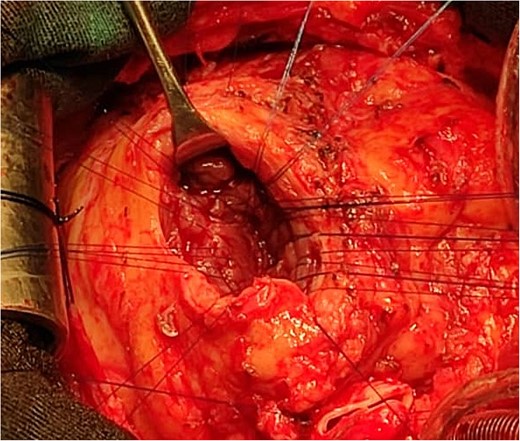

An 11-year-old girl was referred to our hospital with a main complaint of progressive exertional dyspnea. She had undergone surgical repair of SAS 6 years ago. Transthoracic echocardiogram (TTE) revealed the following findings: severe left ventricular hypertrophy, tunnel-like fibromembranous subaortic stenosis with a length of 10 mm, a peak gradient (PG) across the LVOT of 170 mmHg, and mild aortic regurgitation. Based on these findings, the patient was scheduled for elective surgical repair with a possible indication for MKO. The operation was performed via median sternotomy with great caution to avoid inadvertent rupture of any cardiac cavity due to heavy adhesions from the previous operation. The aorta was cannulated just below the takeoff of the innominate artery. Bicaval cannulation was performed to provide a bloodless field. Aortic cross-clamping was applied, and antegrade cold blood cardioplegic solution was administered via a catheter placed in the ascending aorta. The ascending aorta was opened transversely 1 cm above the sinotubular junction (Fig. 1). The aortic valve leaflets were examined carefully to confirm that the aortic valve could be preserved. LVOT was examined thoroughly, and it was clear that the stenosis in the subaortic area was so complex that simple resection through the aortic valve orifice would not be sufficient. The right ventricular outflow tract was opened transversely below the pulmonary valve. The conal papillary muscle was identified (Fig. 2). A right-angle instrument was introduced through the aortic orifice into the interventricular septum, and the tip of the instrument was used to perforate the conal septum to the left of the conal papillary muscle to prevent damage to the conduction system; the septal incision was completed with great caution to avoid damage to the aortic cusps and to extend the incision downward as necessary to completely relieve the stenotic subaortic area (Fig. 3). Interrupted 5/0 Prolene sutures were placed circumferentially around the septal incision to close the interventricular septal defect using a bovine pericardial patch to provide adequate widening of LVOT (Fig. 4). The right ventriculotomy was closed with a second bovine pericardial patch to avoid any possible obstruction of the right ventricular outflow tract (Fig. 5). The remainder of the operation was completed uneventfully. After 6 hours of mechanical ventilation, the patient was extubated, and she convalesced well postoperatively. TTE showed excellent results of the operation with PG across LVOT of 20 mmHg. On 1 year follow-up, the patient was asymptomatic and in very good general condition, and TTE findings confirmed the excellent result.

Intraoperative image showing the interrupted sutures placed around the septal incision.